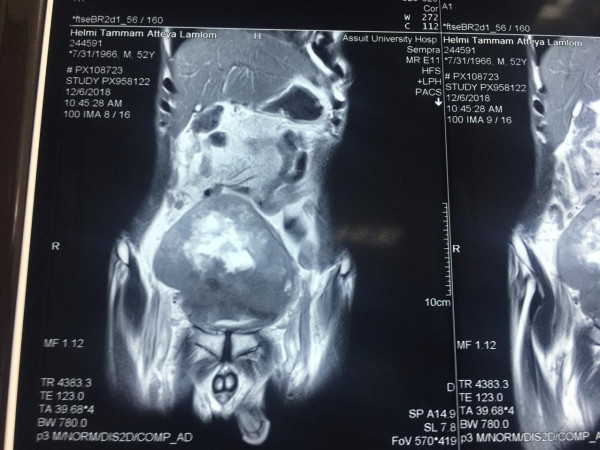

وعن تفاصيل العملية فقد أوضح الدكتور ضياء عبد الحميد الأستاذ بقسم جراحة المسالك البولية والكلى ورئيس وحدة أورام المسالك وقائد الفريق الطبي المسئول عن العملية ، أن تلك العملية تعد من أخطر عمليات استئصال أورام المثانة البولية وذلك نظراً لكبر حجم الورم واختراقه للأمعاء والأنسجة المجاورة من الشرايين والعضلات ، مما يشكل خطورة بالغة على حياه المريض والذي تم تعرضه لظروف معينة تسببت في إهماله للمرض لعدة سنوات، مشيراً أن ذلك تم من خلال التنسيق والتعاون مع أعضاء قسم الجراحة العامة .